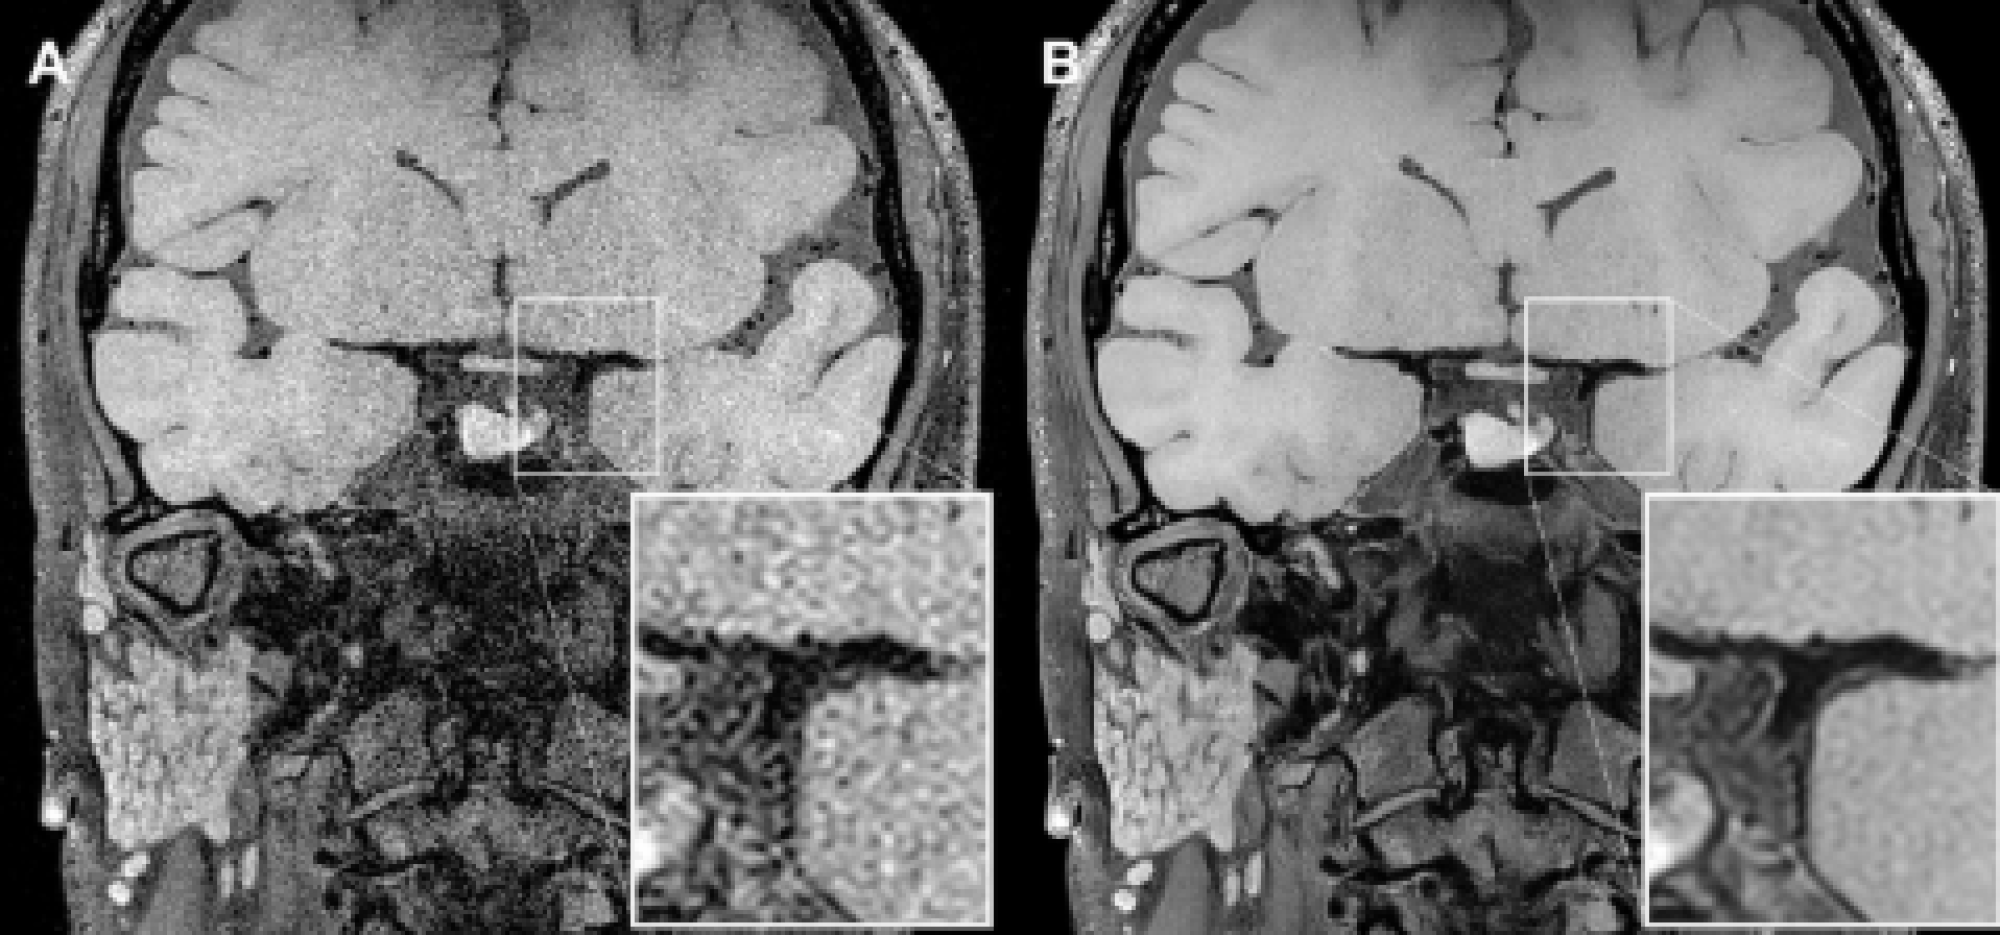

Figura 2: Melhor detecção de lesões na parede arterial: SwiftMR aumenta a nitidez e conspicuidade, facilitando a identificação de hemorragia intraplaca e outras alterações.